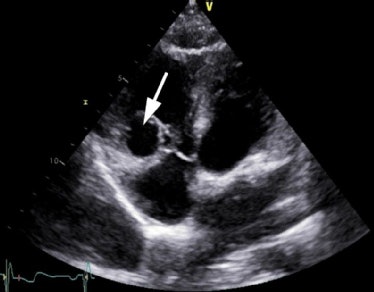

Quiz 4

Transthoracic echocardiography (modified four-chamber view) in a 42-year-old female with atypical chest pain and stress electrocardiogram (ECG), suggesting myocardial ischemia. The arrow points at an unusual structure in the right ventricle.

By Drs. Bogdan Popescu and Roxana Enache, University of Medicine and Pharmacy "Carol Davila" - Euroecolab, Institute of Cardiovascular Diseases "Prof. Dr. C. C. Iliescu," Bucharest, Romania.